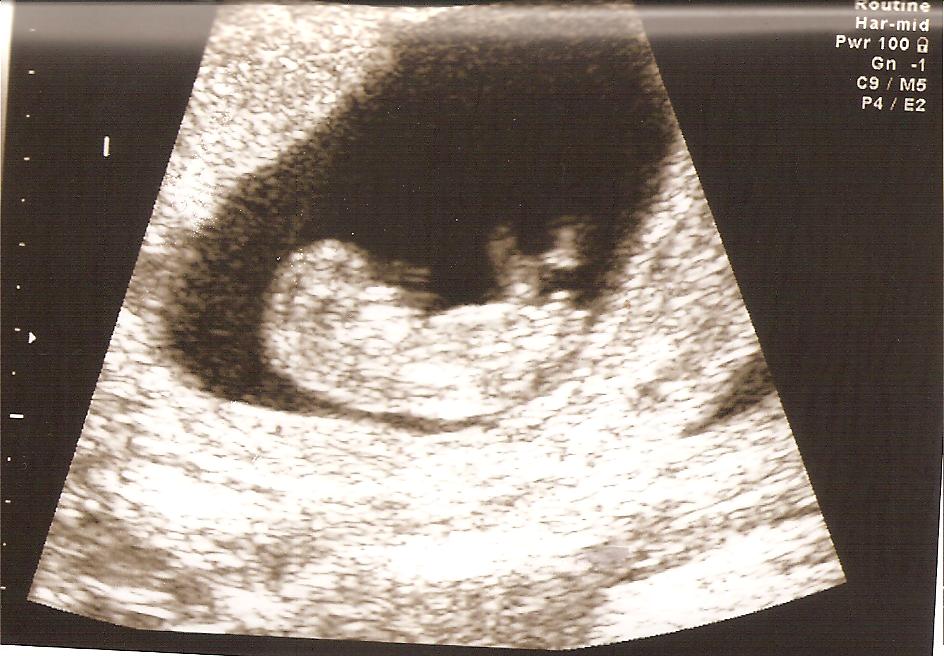

I'm 12 weeks pregnant and almost over the first trimester/sickness hump :) It's been a crazy pregnancy with 3 ultrasounds already but everything is finally looking healthy and I can exercise again :) Pregnancy nausea which turns into very unhealthy eating + no exercise by doctors demands = an awful 6 weeks. Happy to say I went for a run on Monday for the first time in over a month and I enjoyed every minute :)

We're hoping for another one of these...